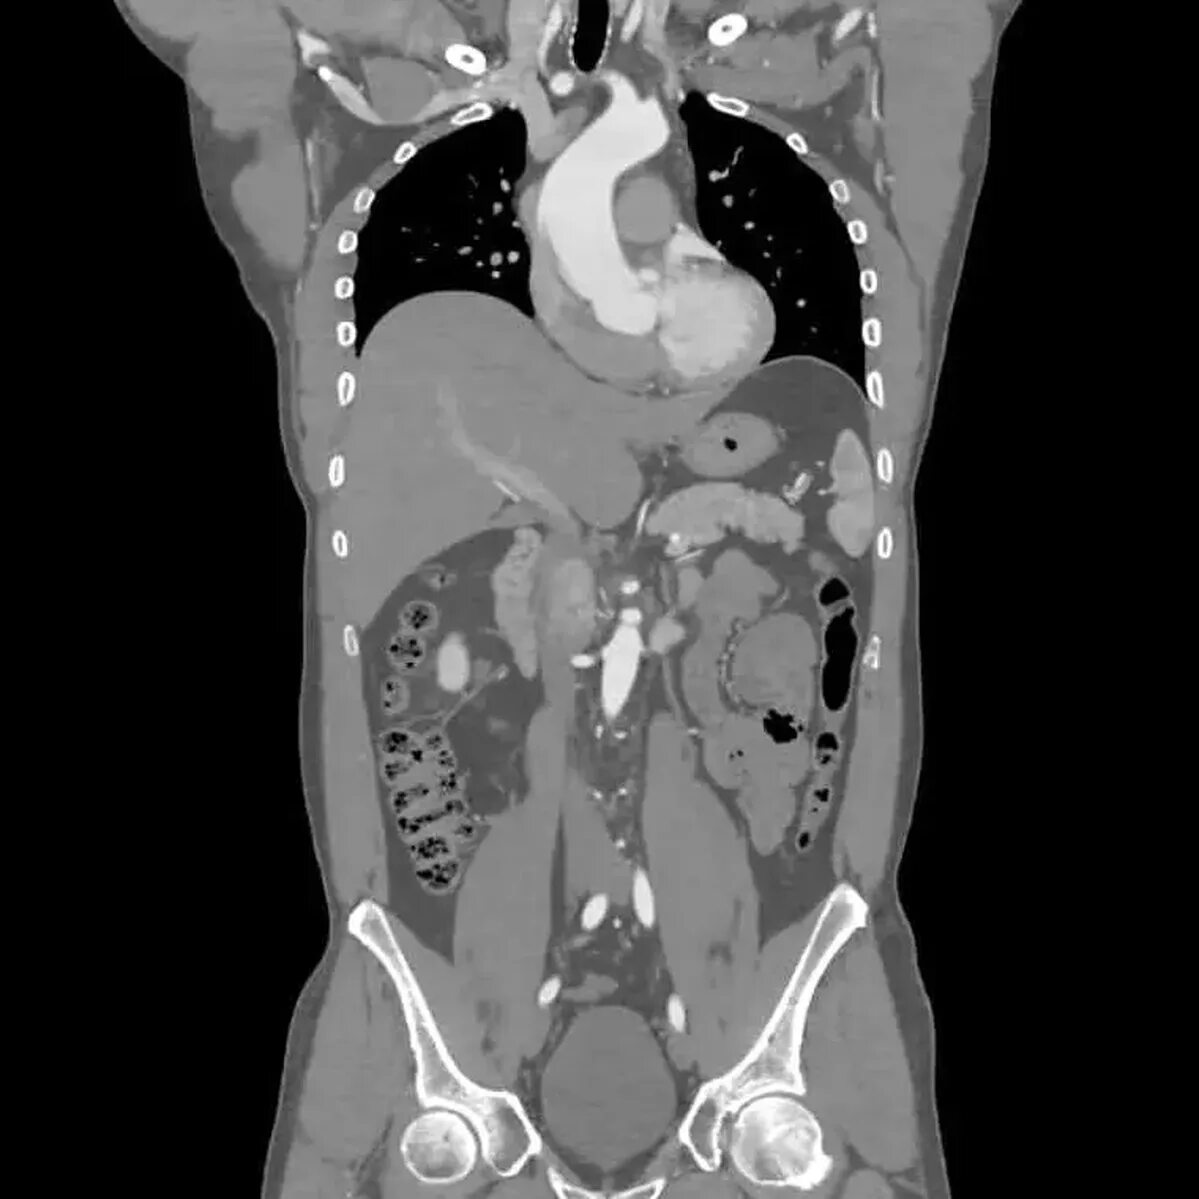

Кт брюшного пространства что показывает